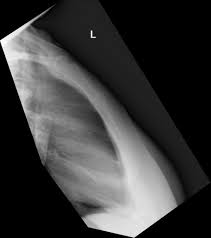

Fractured Sternum Injury Boston Chest Injury Lawyer

Fractured Sternum Injury Boston Chest Injury Lawyer from burnsjainlaw.com